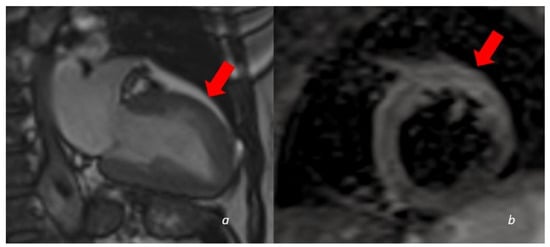

Figure 4.

A 60 y/o woman presenting with acute chest pain and Troponin elevation with ECG alterations in the anterior leads. Echocardiogram showed dyskinesia of the anterior middle wall of the left ventricle. Subsequent cardiac MRI (24 h later) demonstrated dyskinetic movement in the anterior wall of the left ventricle ((a)-cine images frame in the systolic phase showing anterior bulging), associated to edema in the anterior wall (b). No LGE was found in the myocardial wall.